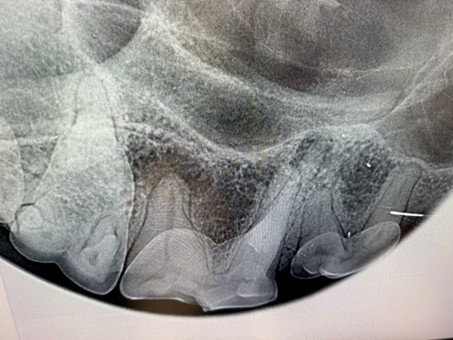

Ein praxisorientierter Schwerpunkt liegt auf der Anfertigung vollständiger Dentalröntgenaufnahmen („full-mouth radiography“) bei Hund und Katze sowie dem präzisen Dental Charting.

3. Dentalröntgen für Hunde und Katzen korrekt anfertigen

- die Grundlagen der intraoralen Dentalradiologie sicher verstehen

- Projektionsgeometrie und Belichtungseinstellungen richtig wählen

- eine vollständige „full-mouth radiography“ bei Hund und Katze durchführen

- häufige Positionierungsfehler erkennen und korrigieren

| 11:45-13:00 Uhr | Zahnröntgen für die Full mouth radiography am Hund und an der Katze |

| 14:00-15:00 Uhr | Übungen am Hunde- und Katzenschädel in 2 Gruppen je 90 min. • Dentaleinheiten Auf-/Abbau (Reinigung und Aufbereitung), Bohrer • Anfertigen von Zahnröntgen in 2 Gruppen |

| 15:30-17:00 Uhr | Übungen am Hunde- und Katzenschädel in 2 Gruppen je 90 min. • Dentaleinheiten Auf-/Abbau (Reinigung und Aufbereitung), Bohrer • Anfertigen von Zahnröntgen in 2 Gruppen |